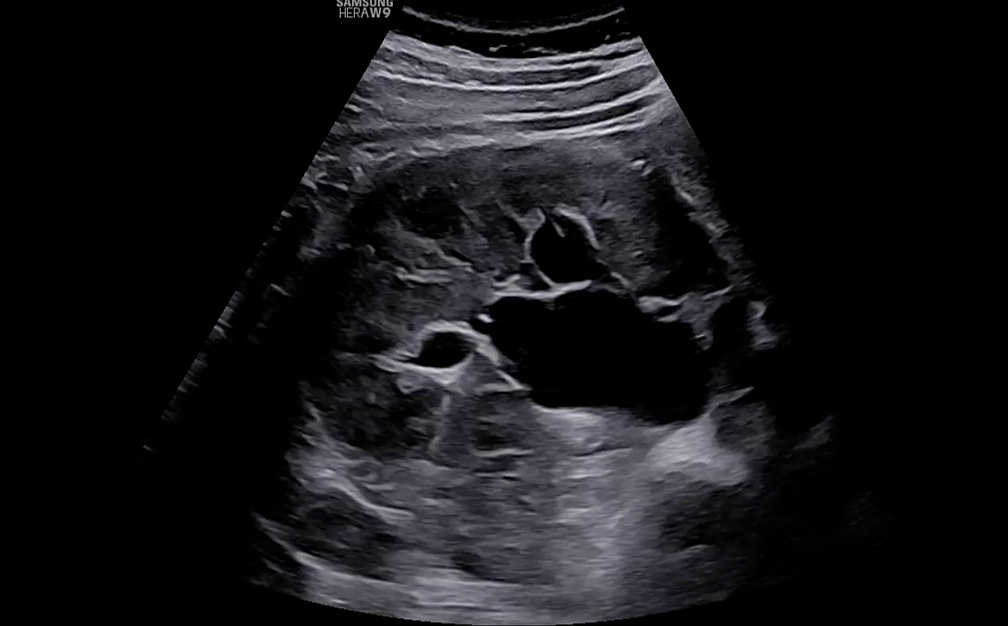

Ureters

Ureteral endometriosis (UE) is classified as extrinsic (fibrotic compression) or intrinsic (intraluminal infiltration), with extrinsic being more common.5 Although UE may be asymptomatic, it carries the risk of progressive hydronephrosis and renal damage. TVS can indirectly identify UE through visualization of hydronephrosis or ureteral dilatation (> 6 mm) and directly as a hypoechoic band or nodule compressing or deviating the distal ureter34 (Figure 13, Video 2).

The distal ureters can be identified laterally and posteriorly to the uterine arteries in the longitudinal plane. Deviation, thickening or reduced mobility of the ureter at this level should raise suspicion of UE involvement. Assessment of ureteral jets with color Doppler is recommended to confirm ureteral patency. In cases of hydronephrosis or loss of ureteric visualization, further imaging, such as renal ultrasound (Figure 14), computed tomography (CT) scan or MRI scan, should be considered.32

Both ureters and kidneys should be systematically evaluated in all patients with DE, particularly when sacrouterine ligament (SUL) or parametrial nodules are present. Ureteral involvement is often underestimated yet has significant surgical and functional implications.33,35

14

Renal assessment is an essential part of the endometriosis ultrasound protocol. Up to 3% of patients present with silent hydroureteronephrosis.